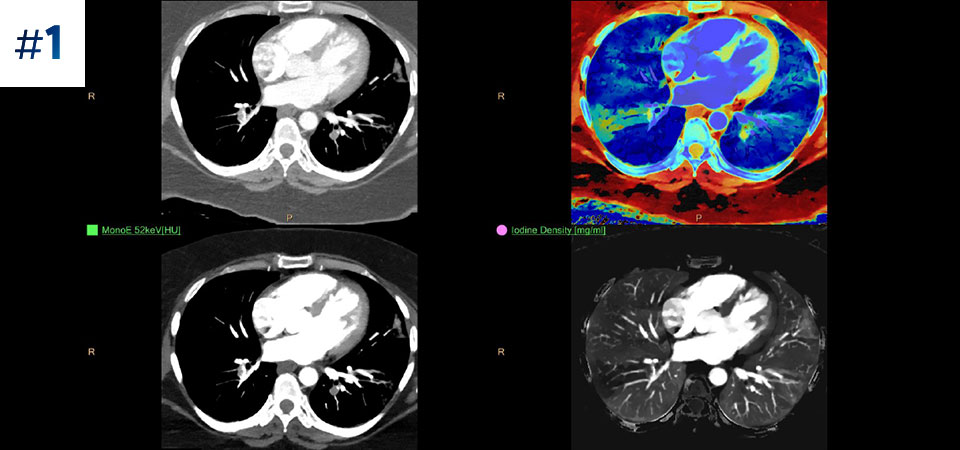

With detector-based spectral, you acquire multiple layers of data—conventional and spectral—within a single exposure and without special scan modes for improved tissue characterization and visualization.

Scan as usual A single scan for fast, low-dose conventional and spectral data for every patient, every time.

Always available 100% spectral, 100% of the time for results that are always available on-demand, even retrospectively.

See the difference between spectral-detector CT and conventional CT

Learn about the advantages of spectral-detector CT